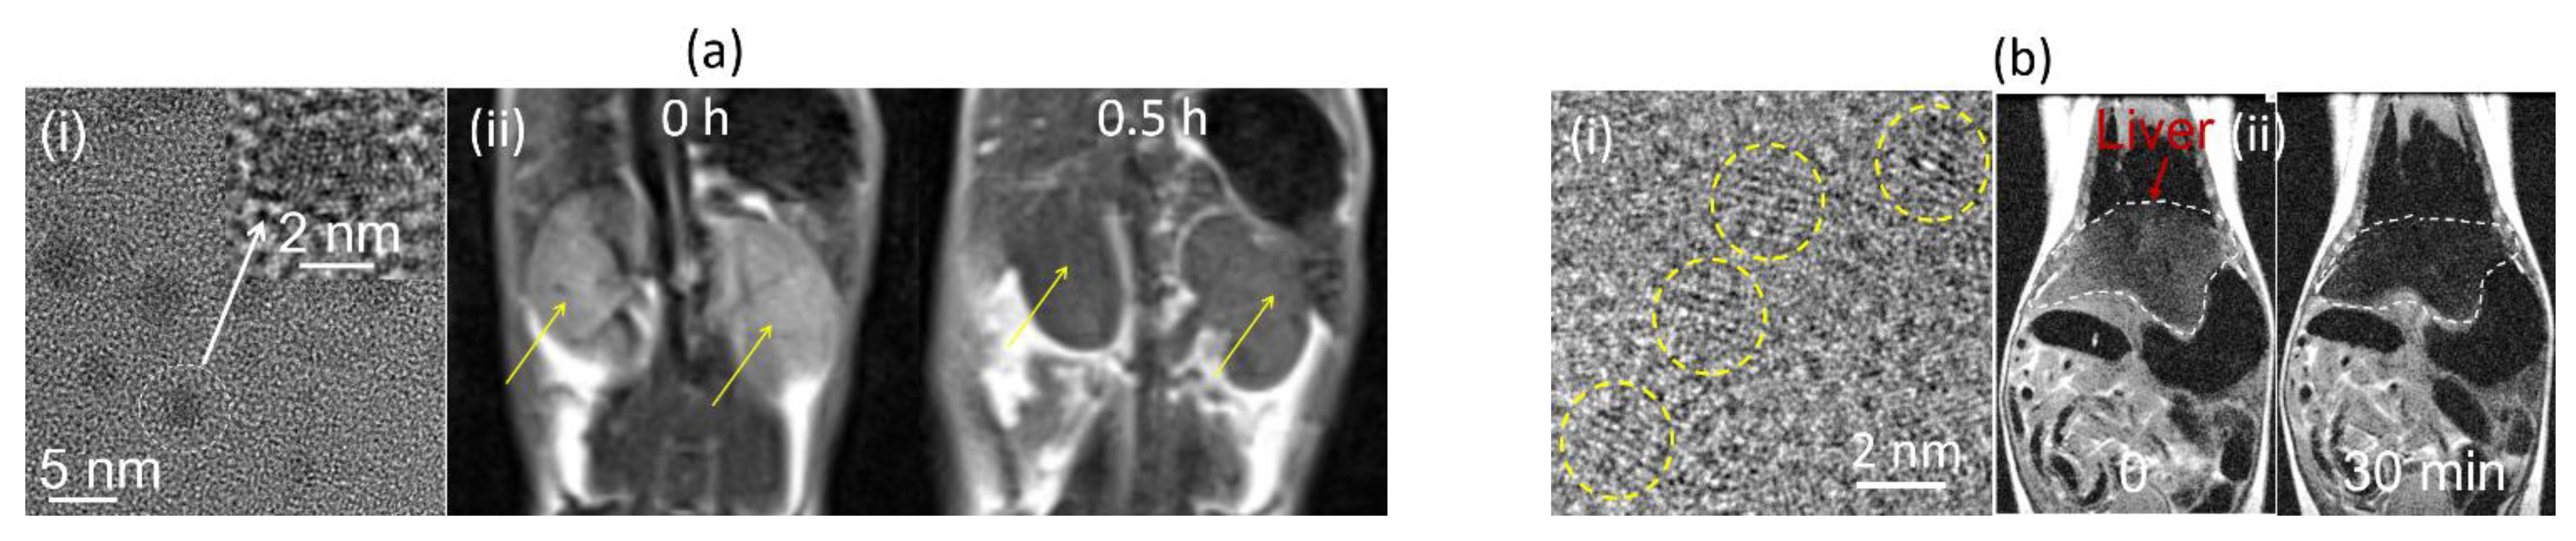

- Wei, R.; Liu, K.; Zhang, K.; Fan, Y.; Lin, H.; Gao, J. Zwitterion-Coated Ultrasmall MnO Nanoparticles Enable Highly Sensitive T1-Weighted Contrast-Enhanced Brain Imaging. ACS Appl. Mater. Interfaces 2022, 14, 3784–3791. [Google Scholar] [CrossRef]

- Li, J.; Wu, C.; Hou, P.; Zhang, M.; Xu, K. One-pot preparation of hydrophilic manganese oxide nanoparticles as T1 nano-contrast agent for molecular magnetic resonance imaging of renal carcinoma in vitro and in vivo. Biosens. Bioelectron. 2018, 102, 1–8. [Google Scholar] [CrossRef]

- Xiao, J.; Tian, X.M.; Yang, C.; Liu, P.; Luo, N.Q.; Liang, Y.; Li, H.B.; Chen, D.H.; Wang, C.X.; Li, L.; et al. Ultrahigh relaxivity and safe probes of manganese oxide nanoparticles for in vivo imaging. Sci. Rep. 2013, 3, 3424. [Google Scholar] [CrossRef]